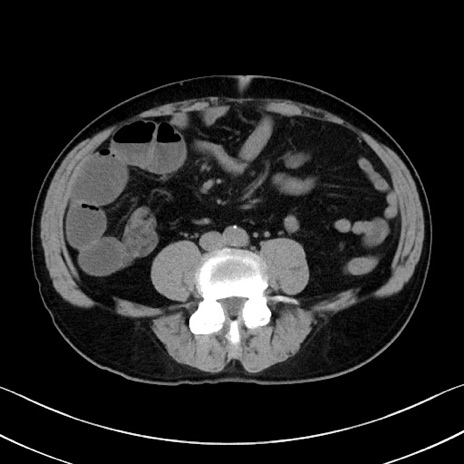

症例35(横断像)

【症例】70歳代 男性

【主訴】腹部膨満、嘔吐

【現病歴】昨日より腹部膨満感出現。本日増悪し、仙痛出現。嘔吐あり、受診。

【既往歴】糖尿病、胆摘後

【身体所見】BP 149/80mmHg、HR 74/min、BT 35.9℃、腹部:膨満、軟、圧痛なし。腸雑音減弱あり。上腹部正中切開瘢痕あり。

【データ】WBC 13500、CRP 1.72